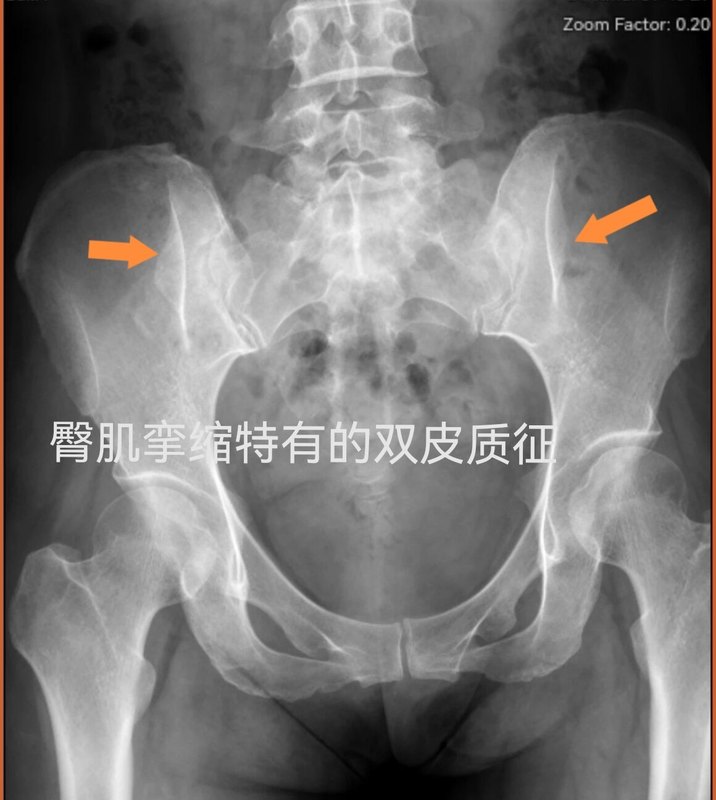

骶髂关节双皮质征-臀肌挛缩证据之一。

臀肌挛缩症,尽管一系列症状都很典型,但对不熟悉这个疾病的人来说,不管是医生还是患者,有时候还很难确诊。什么是双皮质征呢?儿童时臀肌注射苯甲醇等药物形成的挛缩带,不能和骨骼同步生长,反而将骨盆拉变形。具体表现有髂骨外翻、骨盆后倾、髋关节总体外翻、股骨外旋和会阴(耻骨联合)凸起等。其中骶髂关节附近的髂骨外板内陷与X线平行,遮挡更多的X线,在胶片上就形成白线。这也是确诊臀肌挛缩症的客观依据之一。